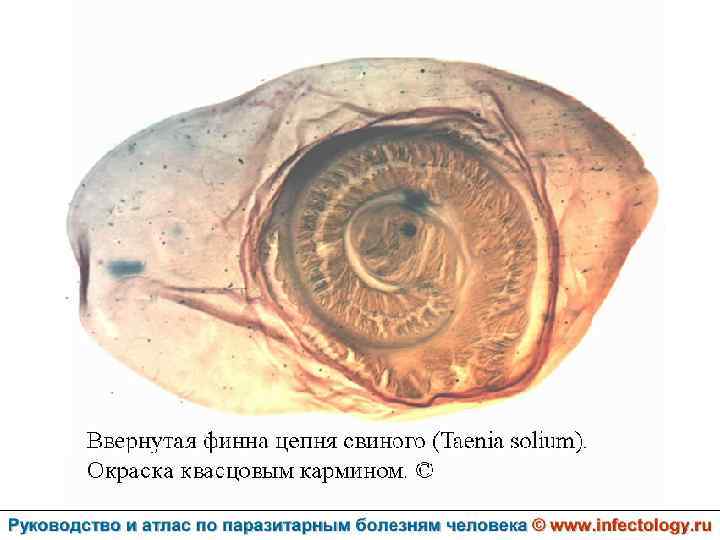

Цистицеркоз (шифр по МКБ 10 - B 69) – биогельминтоз, который вызывается паразитированием в тканях и органах человека и животных личиночной стадии цепня вооруженного – цистицерка (Cysticercus cellulosae) Болезнь проявляется разнообразными симптомами в зависимости от локализации цистицерков.